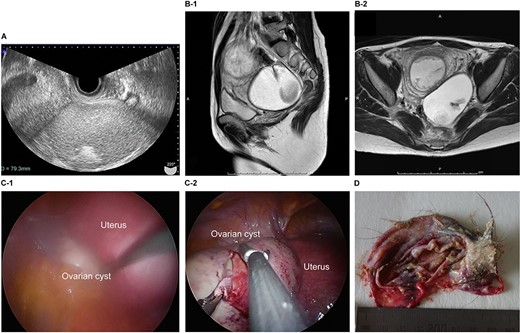

The patient was a 29-year-old, gravida 1, para 0 woman with no familial or medical history. She conceived naturally and was diagnosed a left ovarian cyst at 7 weeks of gestation by another doctor. She was referred to our hospital for further examination and operation. TVUS revealed a fetus in the uterus and a mass 7 cm in diameter on the left ovary, which appeared to be a dermoid cyst. MRI revealed left ovarian cystic tumors with fat tissue. The laboratory values, including levels of tumor markers (e.g. CEA, CA-125, CA 19-9 and SCC) were within the normal limits. We performed single-port laparoscopic surgery at 15 weeks and 3 days gestation to remove the left ovarian cysts. The procedure was performed within 99 minutes, and there were no complications (Fig. 3).

Imaging studies and laparoscopic views and specimen photograph of case 3. (A) Transvaginal ultrasound image showing an ovarian cyst. (B-1) Sagittal T2-weighted MRI showing an ovarian cyst. (B-2) Axial T2-weighted MRI showing an ovarian cyst. (C-1) Gestational uterus: ovarian cyst was moved from the pouch of Douglas. (C-2) Ovarian cyst was moved and located on the gestational uterus. (D) Ovarian Cyst.